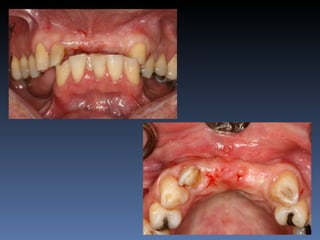

Diagnóstico: Desdentado parcial

pré-maxila.

Plano de tratamento: Reabilitação pré-maxila com

instalação de 2 implantes endo-ósseos (1.1,.2.2), para

reabilitação protética fixa.